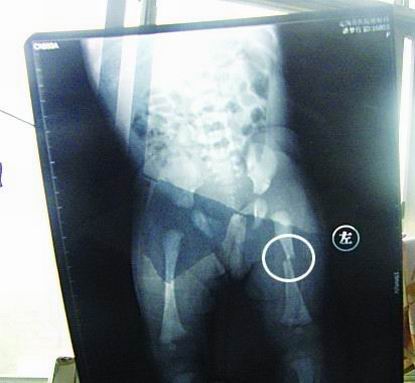

CT顯示小夢(mèng)竹左下肢骨折

今年7月2日下午,定陶縣南王店鄉(xiāng)沈莊村孕婦聶元真,在定陶縣人民醫(yī)院剖腹產(chǎn)下一女?huà)耄∶麨榕藟?mèng)竹。醫(yī)院說(shuō),嬰兒出生后窒息,診斷為新生兒缺血缺氧性腦病,頭皮血腫。當(dāng)晚發(fā)現(xiàn)女?huà)胱笙轮课划惓#诙炫钠@示為左下肢骨干骨折。7月3日,潘夢(mèng)竹的頭顱CT顯示其頭頂部骨折,蛛網(wǎng)膜下腔出血,顱內(nèi)血腫。